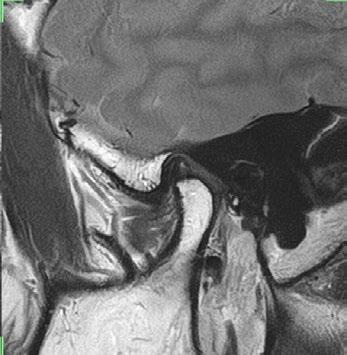

TMJ

16ch Flex SPEEDER, PD, AiCE + Compressed SPEEDER, Res: 0.16 x 0.16 x 2 mm, Scan time: 1:09 min per side.